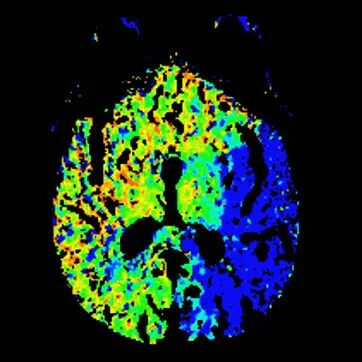

查体BP 160/89mmHg,清醒,双眼左侧凝视位、不可纠正,混合性失语,右侧中枢性面舌瘫,右侧肢体肌力0级,右侧病理征阳性。NIHSS评分18分。随机血糖4.8mmol/L。心电图:正常。颅脑CT无出血及新发梗死灶,多模态CT示左侧大脑中动脉闭塞、左侧大脑半球低灌注。

多模态CT。